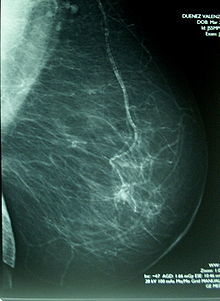

UTILIDAD DE LA MAMOGRAFIA PARA LA DETECCION DE C.A DE MAMA

MAMOGRAFIA: estudio de oro en la deteccion temprana unico metodo validado para escrotinio , detecta lesiones temprana